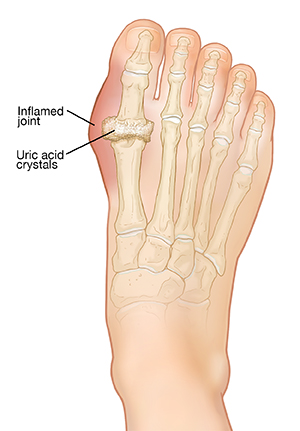

Gout is a form of arthritis caused by too much uric acid buildup in your body. Gout often causes sudden pain and swelling in 1 joint, often the big toe or other joints in the feet. If not treated, it can lead to painful foot and joint deformities. It may lead to kidney problems. But by treating gout early, you can ease pain and help prevent future problems. Gout can often be treated with medicine and a change in diet. In severe cases, surgery may be needed.

Gout is caused by too much uric acid in the body. This is a waste product made by the body. Uric acid is filtered out by the kidneys. If the uric acid level in your blood rises too high, it may form crystals. If these crystals are not treated and are kept in the body for a long time, they will cause severe health issues. These collect in the joints. This brings on a gout attack. A gout attack is inflammation in the joints that can cause sudden pain and swelling. If you have many gout attacks, crystals may form large deposits called tophi. Tophi can damage joints and cause deformity.